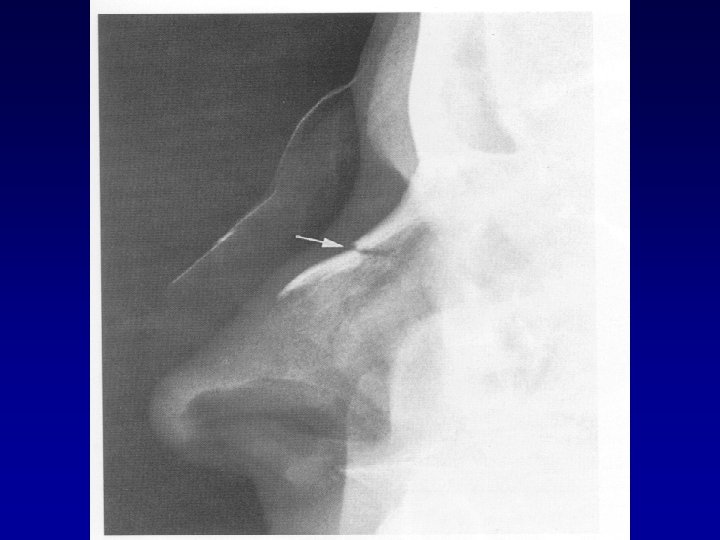

benjamin p 86, fig 2 -13